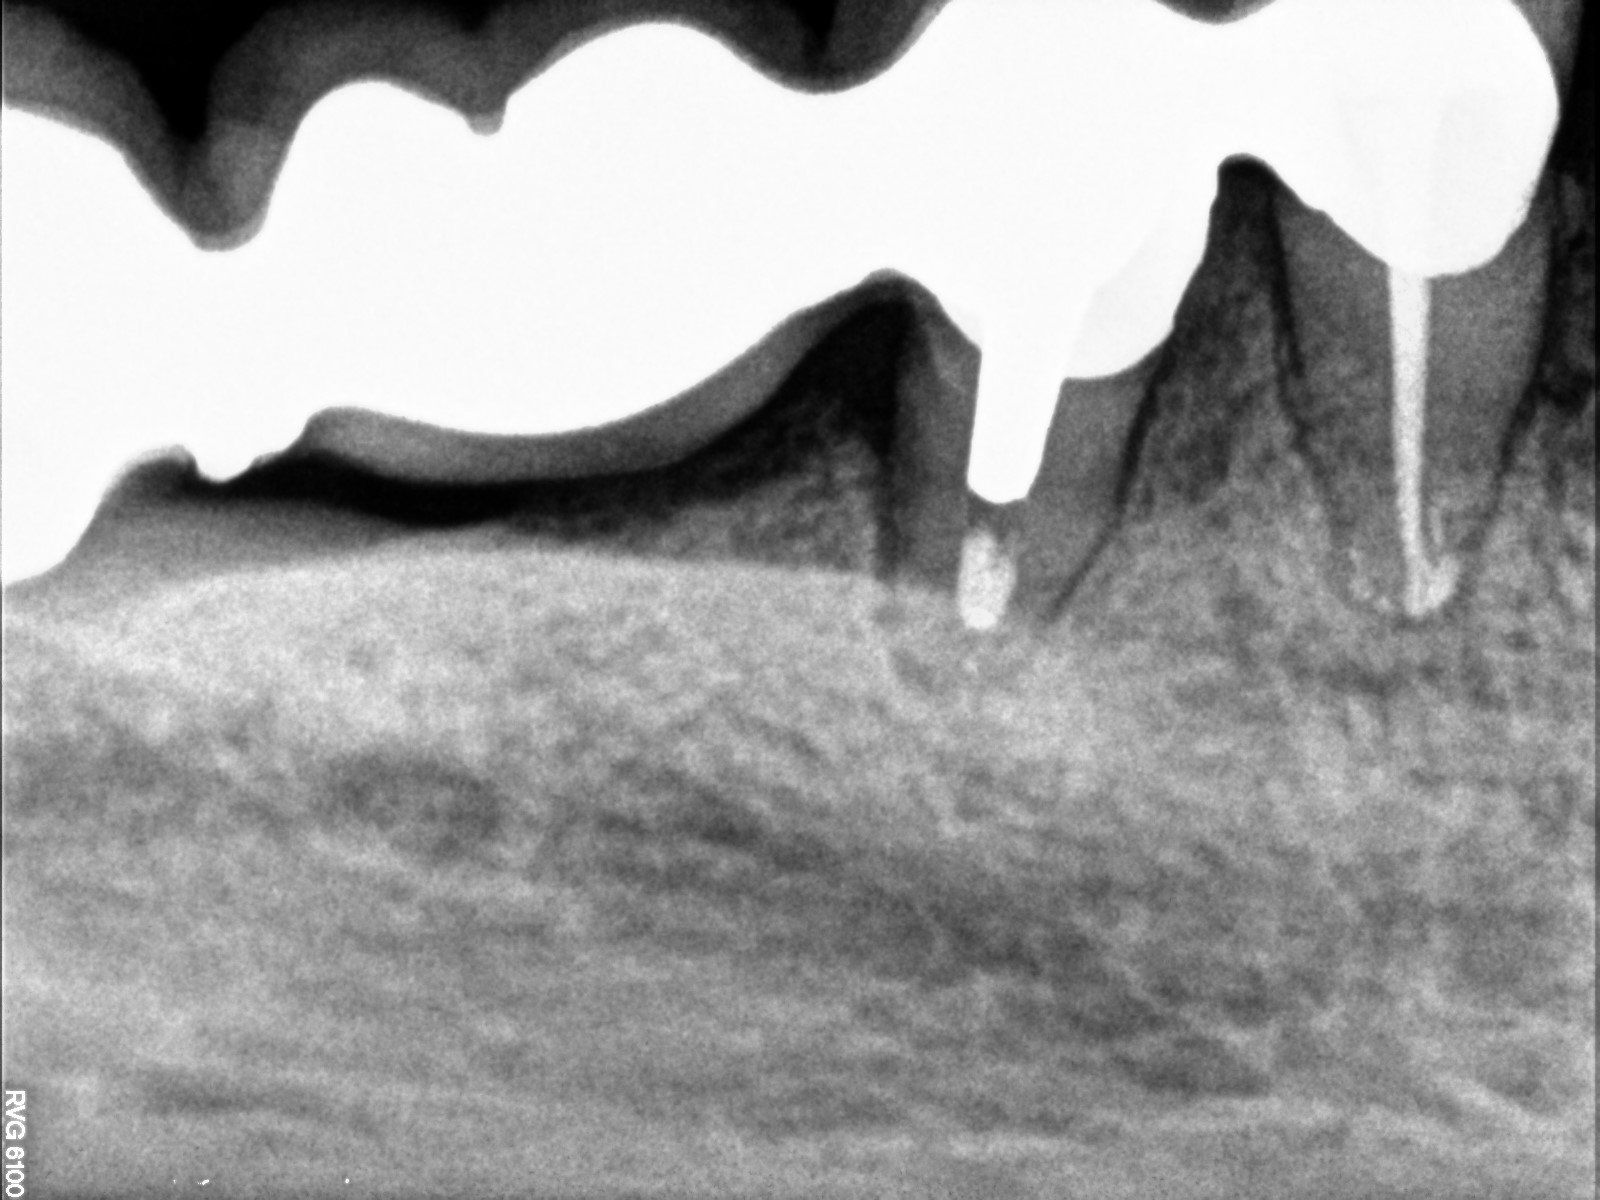

(la terza e quarta radiografia illustrano la devitalizzazione del dente senza l'eliminazione della capsula esistente ma solo con perforazione e ricostruzione nel punto preciso su capsula esistente).